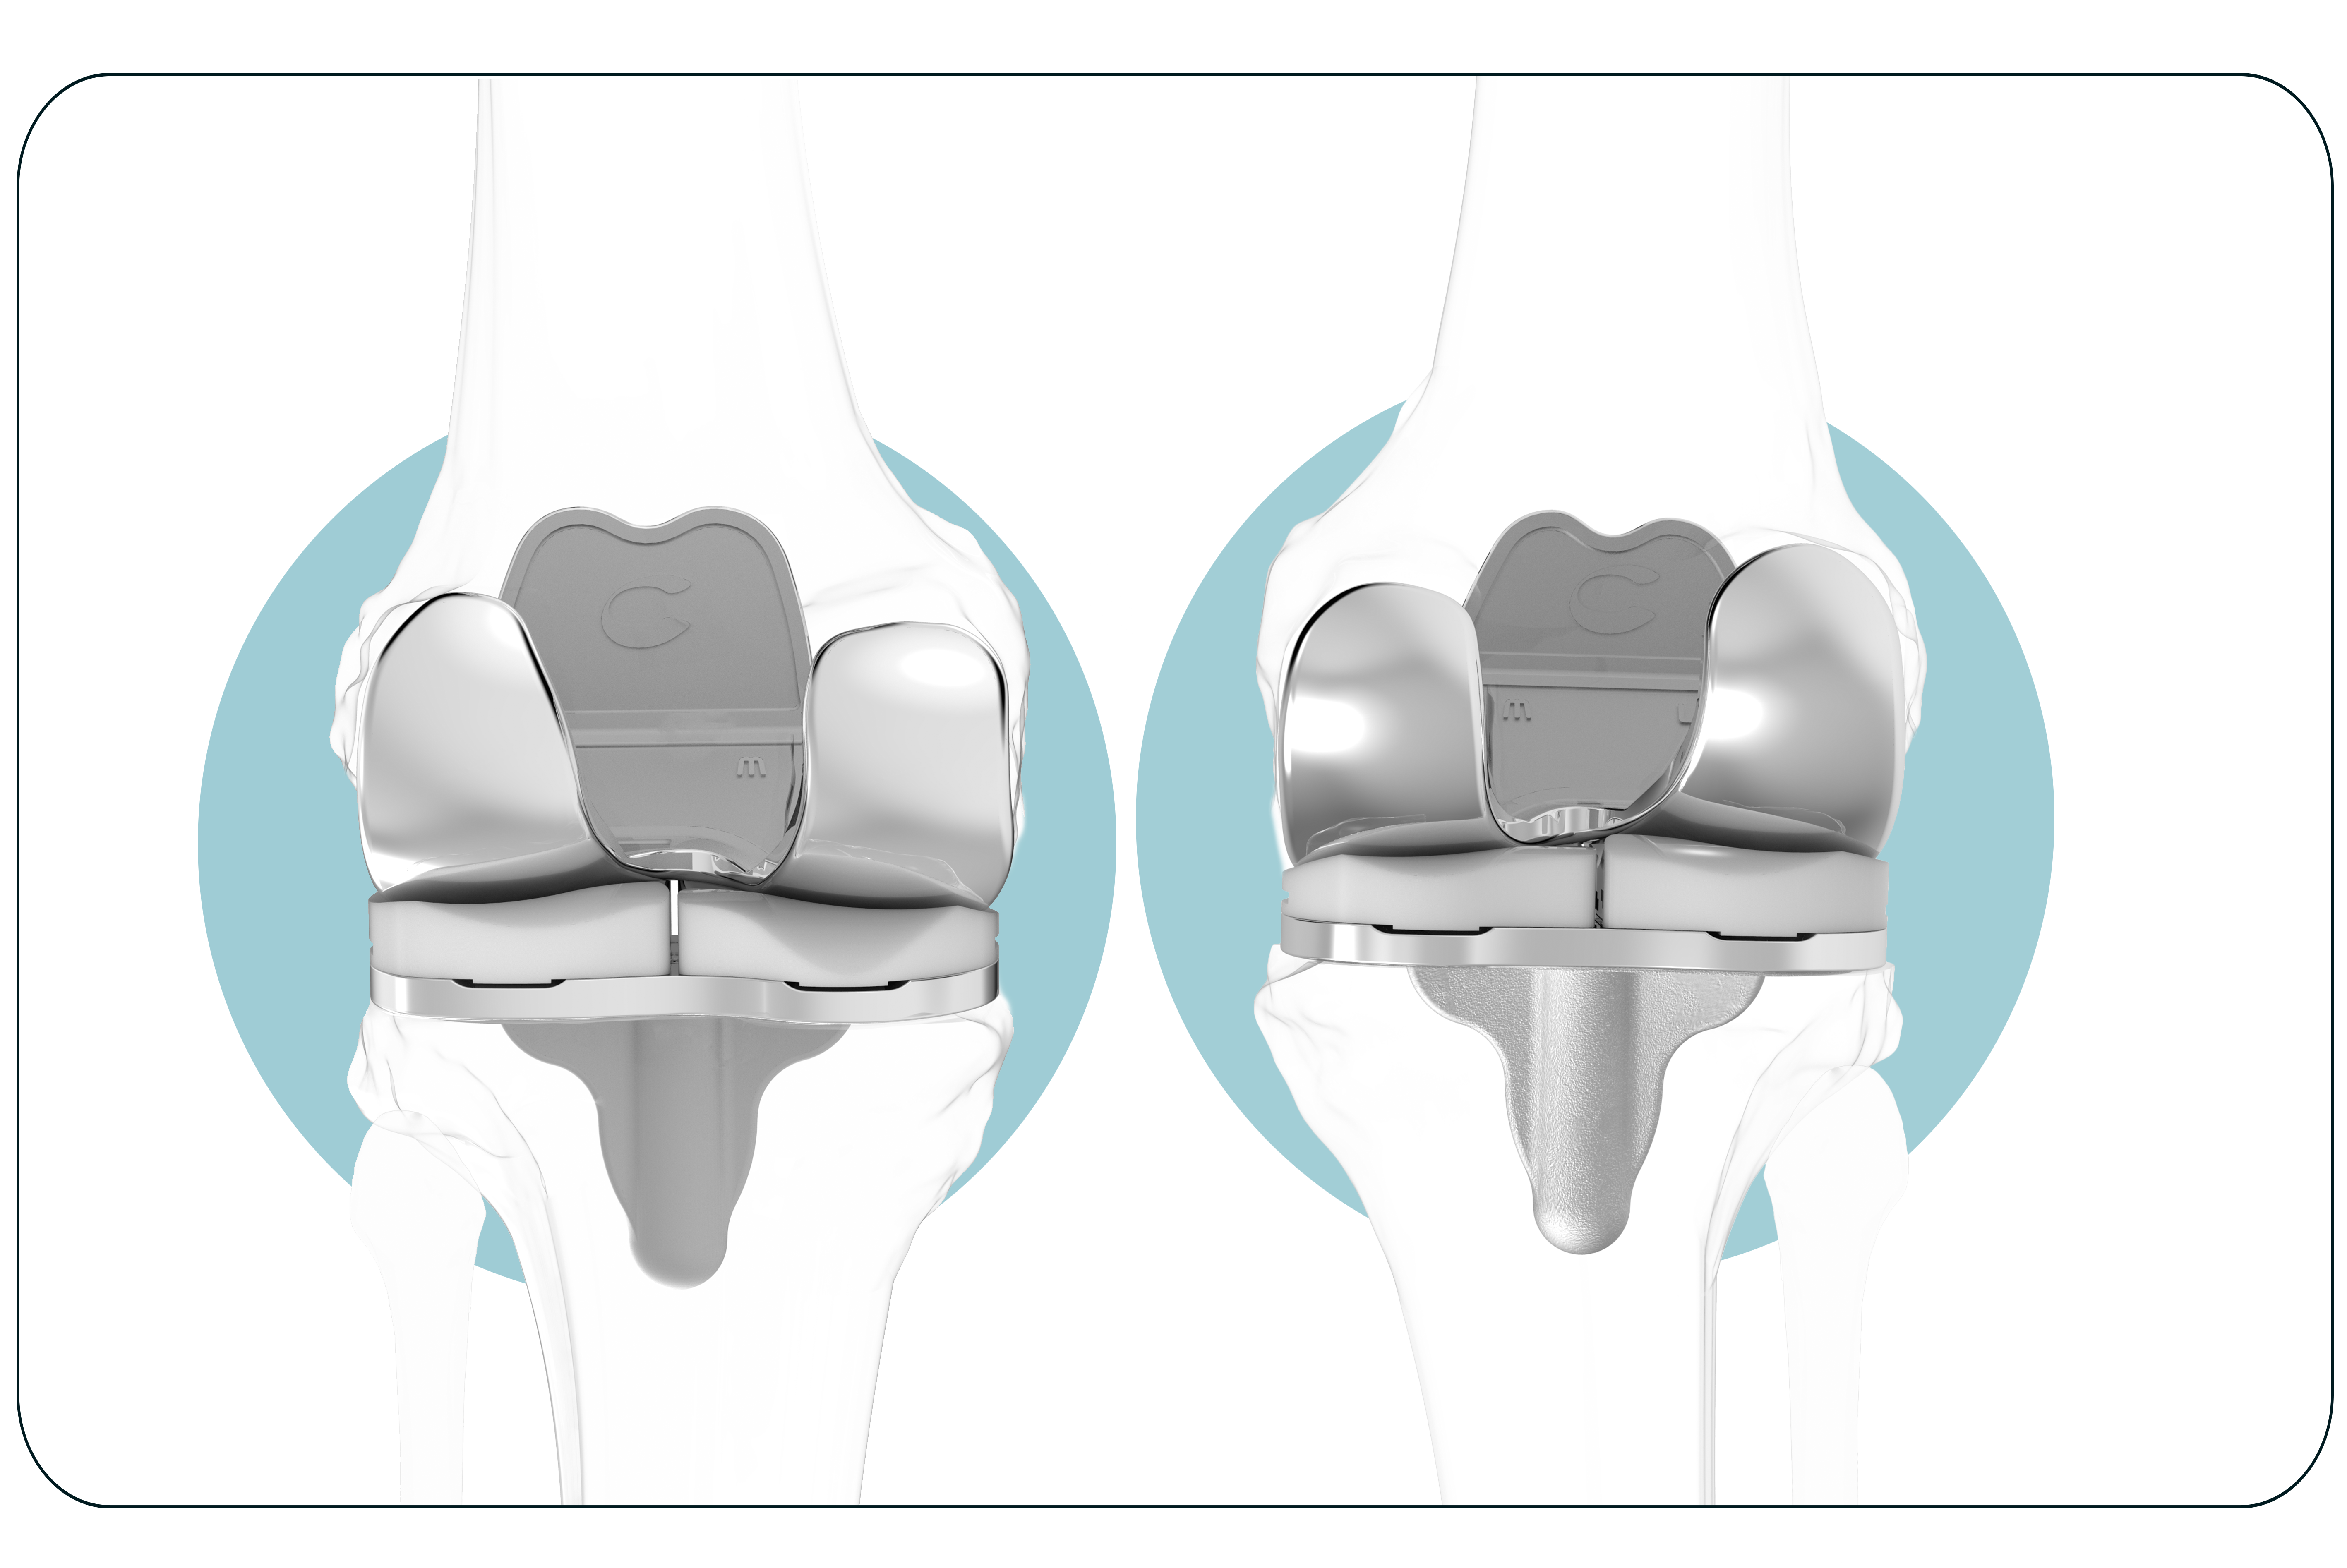

Un paciente. Un implante

Ajuste individualizado

que prácticamente elimina las dolencias ocasionadas en pacientes con otro tipo de prótesis de rodilla.

Consigue una sensación más natural

Prótesis de rodilla 3D está diseñada para seguir la forma y el contorno de la rodilla de cada paciente, proporcionando un mayor potencial para su rodilla con una sensación más natural.

Evita la inestabilidad

Mantiene las líneas naturales de la articulación del paciente para evitar la inestabilidad, causa común de la insatisfacción del paciente.